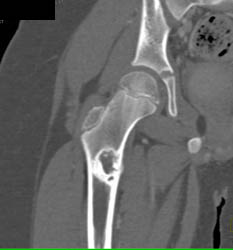

Rotator Cuff Tear on CT Arthrogram